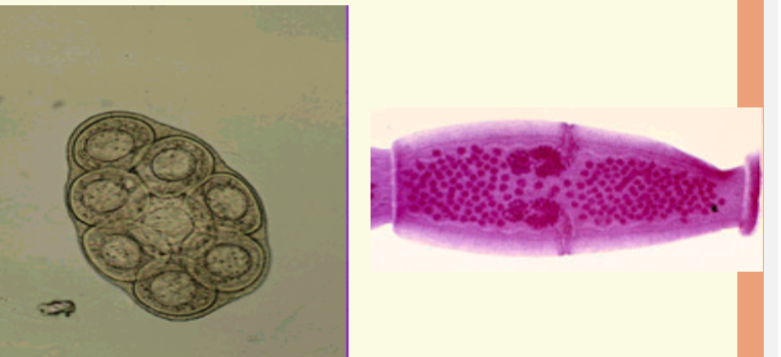

Taenia spp ova

Taenia spp proglottids

H. nana ova

The diagnostic stage

4 Oval or sub spherical

4 Colorless

4 47 x 37 um

4 Shell consists of two distinct membranes

4 Contains embryonated, 6 hooked

Onchosphere

4 4 - 8 filaments arise from polar ends

4 Filaments arise from polar knobs

H. nana lab diagnosis

Recovery and

identification of ova in

feces

4 50 x 30

um

4 thin, colorless shell

4 filaments emerge from

polar thickenings

4 contains hexacanth

embryo

– six tiny hooklets (3

pair)

H. diminuta ova

Similar to

4 58 x 86 um

4 has thick outer shell,

yellow

4 colorless inner shell

(onchosphere)

4 3 pairs of hooklets

present

4 no polar filaments

from inner membrane.

– Distinguishes it form

H.

nana

size comparison chart

cestode ova comparison